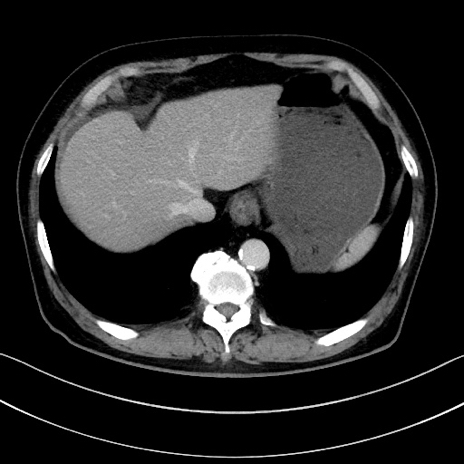

症例15(横断像)

【症例】70歳代男性

【主訴】腹痛

【現病歴】今朝から腹痛あり。全体的に痛い。特に左上の方。排ガスが今日はない。冷や汗が出る。

【既往歴】直腸癌術後

【身体所見】左側腹部〜上腹部に圧痛あり。腹膜刺激症状明らかなではない。軽度反跳痛。左下腹部に術後瘢痕あり。

【データ】WBC 7700、CRP 0.02